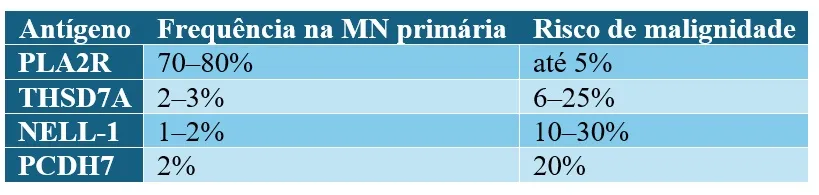

Antígenos como pistas diagnósticas

PLA2R positivo não exclui completamente câncer, mas THSD7A e NELL-1 devem acender o alerta vermelho.

4. Antígenos como PLA2R, NELL-1 e THSD7A ajudam a diferenciar GN primária de paraneoplásica?

* Ausência de anticorpos PLA2R e padrão histológico atípico

* Presença de THSD7A ou NELL-1